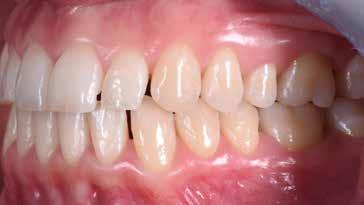

Presentazione del caso > F.V, bambino di cinque anni, presenta una malocclusione di II Classe scheletrica, III Classe dentale molare e canina destra e sinistra, morso inverso anteriore. Le arcate dentali mostrano usura degli elementi dentari anteriori a causa dell’occlusione patologica. Le linee mediane, superiore ed inferiore, sono centrate; il frenulo labiale superiore patologico per un’eccessiva estensione inter-incisale.

Dall’esame clinico si evince la III Classe dentale, l’inversione anteriore e l’over-jet negativo.

Una volta ottenuta la correzione del rapporto molare ed incisale, l’apparecchio elastodontico verrà portato dal paziente solo durante la notte per stabilizzare il risultato ottenuto e guidare l’eruzione degli elementi dentari per un totale di quattordici mesi di terapia. ad inizio trattamento :

Considerazioni > L’analisi cefalometrica ad inizio trattamento dimostra la II Classe scheletrica con protrusione del mascellare superiore e prognazia mandibolare; tendenza alla crescita verticale. L’esame clinico evidenzia una protrusione mandibolare funzionale.

55 54 ESTETICA FUNZIONE POSTURA Valori cefalometrici ad 1 anno di terapia : ANB ANB 3,8 Posizione del Mascellare SNA 91.40 Posizione della Mandibola SNB 87,60 Angolo Articolare SArGo 155,00 Angolo Goniaco ArGoMe 122,00 Angolo incisivo inf^Corpo madibolare IiMand 80,20 Angolo incisivo Sup^Base Cranica Ant. IsCran 111,05 Angolo Interincisivo II 138,00 72, 73 _ Over-bite e over-jet. 74 _ Immagine laterale destra. 75 _ Immagine laterale sinistra. Considerazioni > La terapia precoce di tali malocclusioni è di primaria importanza in quanto impedisce la formazione di malocclu-